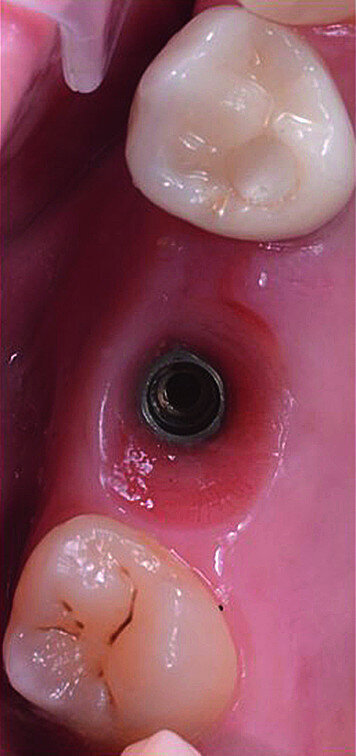

Once the implant bed had been prepared, a 7 × 10 mm implant (AnyRidge) was placed. After placement, the ISQ (Implant Stability Quotient) was measured with a stability meter (Mega ISQ, MegaGen), and the value was 72. According to the ISQ scale, this represents high stability (Fig. 6b). A 10 × 7 mm healing screw (AnyRidge) was placed, along with a plug of A-PRF (advanced platelet-rich fibrin; PRF process by Choukroun) in order to accelerate the healing process, and sutured with 4/0 polypropylene (Hu-Friedy; Figs. 7–10). After the surgical procedure, the White Clinic postoperative protocol was applied: application for eight minutes of the ATP38 laser (Swiss Bio Inov), based on the principle of Low Level Laser Therapy that acts on the cellular metabolism and provides a better and faster postoperative healing. The patient was instructed to use a 0.2% hyaluronic acid gel (Gengigel, Ricerfarma) and 0.1% hyaluronic acid mouthwash (Gengigel First-aid, Ricerfarma) for one week after surgery, with the goal of accelerating the healing process. One week after surgery, the sutures were removed, ozone was used to disinfect the area around the implant, and the ATP38 was applied for eight minutes to promote healing.

In March 2018, four months after the surgery, the prosthetic phase was started. An impression was taken with an intraoral scanner (CS 3600, Carestream Dental) using scan bodies for an impression at the implant head (MegaGen; Figs. 11a & b). The information was sent to the Anatomic Lab, where a crown was designed using a CAD programme. After the design of the crown had been finished, the information was sent to a milling machine (Amann Girrbach) and the crown was milled (Fig. 12). One week after the preparation, the definitive crown in monolithic zirconia was attached and the occlusion tested using T-Scan technology (Tekscan; Figs. 13a–c & 14).